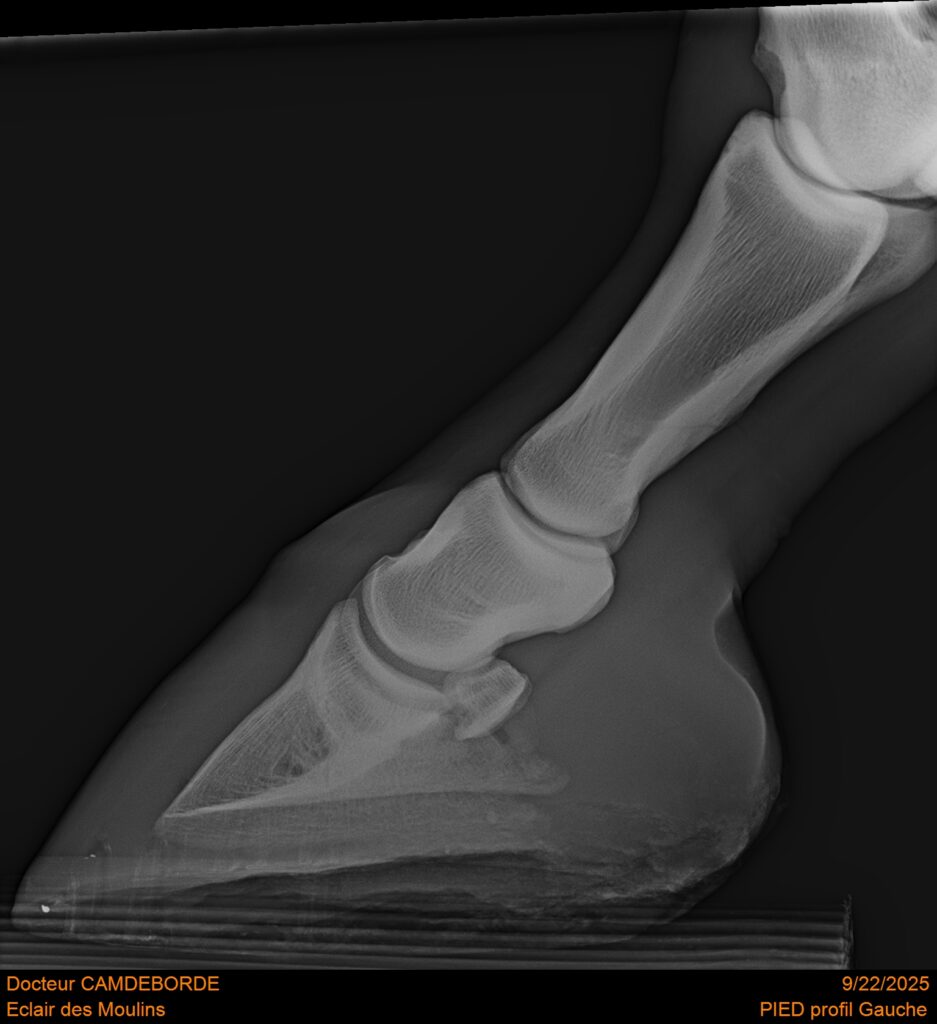

RADIOS ET CLINIQUE